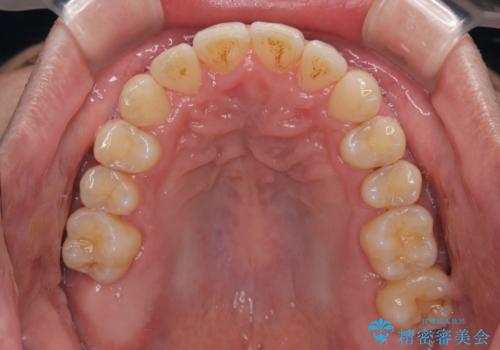

- 上下前歯のデコボコを気にして来院された患者様です。

上顎前歯の舌側転位が顕著であったため、治療期間が長くなると思われましたが、僅か1年で無事に終えることができました。